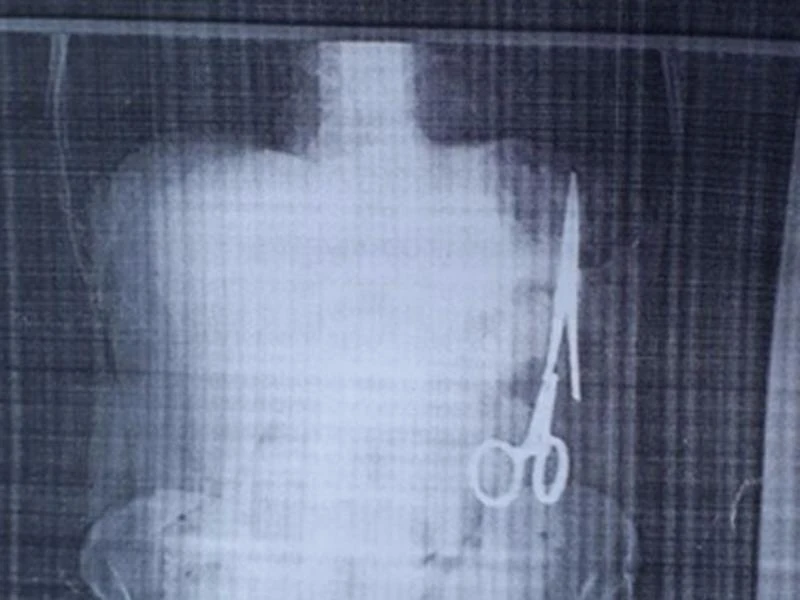

Chiếc kéo/panh được cho là đã nằm trong bụng bệnh nhân 18 năm. Ảnh: TTXVN

Theo một thành viên kíp mổ, mặc dù nằm trong ổ bụng bệnh nhân tới hơn 18 năm nhưng chiếc panh chỉ bị rỉ sét một chút ở phần đầu. Panh nằm ở bên trái của ổ bụng, sát đại tràng. Một số bộ phận trong cơ thể bệnh nhân do tiếp xúc dị vật lâu ngày đã có dấu hiệu dính sát vào panh.